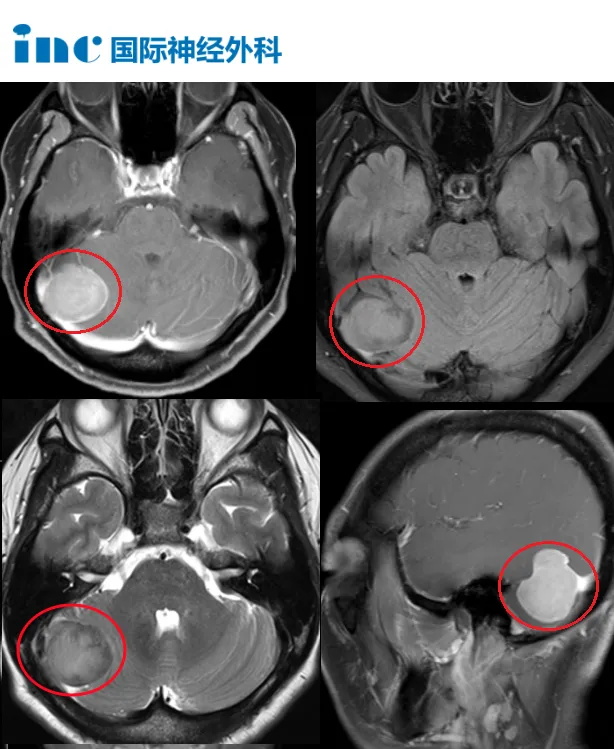

桥小脑角区 脑膜瘤 ,通常压迫周围许多重要神经血管、小脑甚至脑干,大肿瘤,手术难度大,手术不慎易残留肢体瘫痪、面瘫、听力损伤等。完整切除桥...

CPA桥小脑角区脑膜瘤案例:INC巴教授顺利切CPA区桥小脑角区脑膜瘤疑难手术,面、听神经完好保留...

CPA桥小脑角区肿瘤约占成人全部颅内肿瘤的10%。脑膜瘤是二常见的肿瘤官方认可的桥小脑角区肿瘤,前庭神经鞘瘤之后,是生长缓慢的良性病变,通常可以...